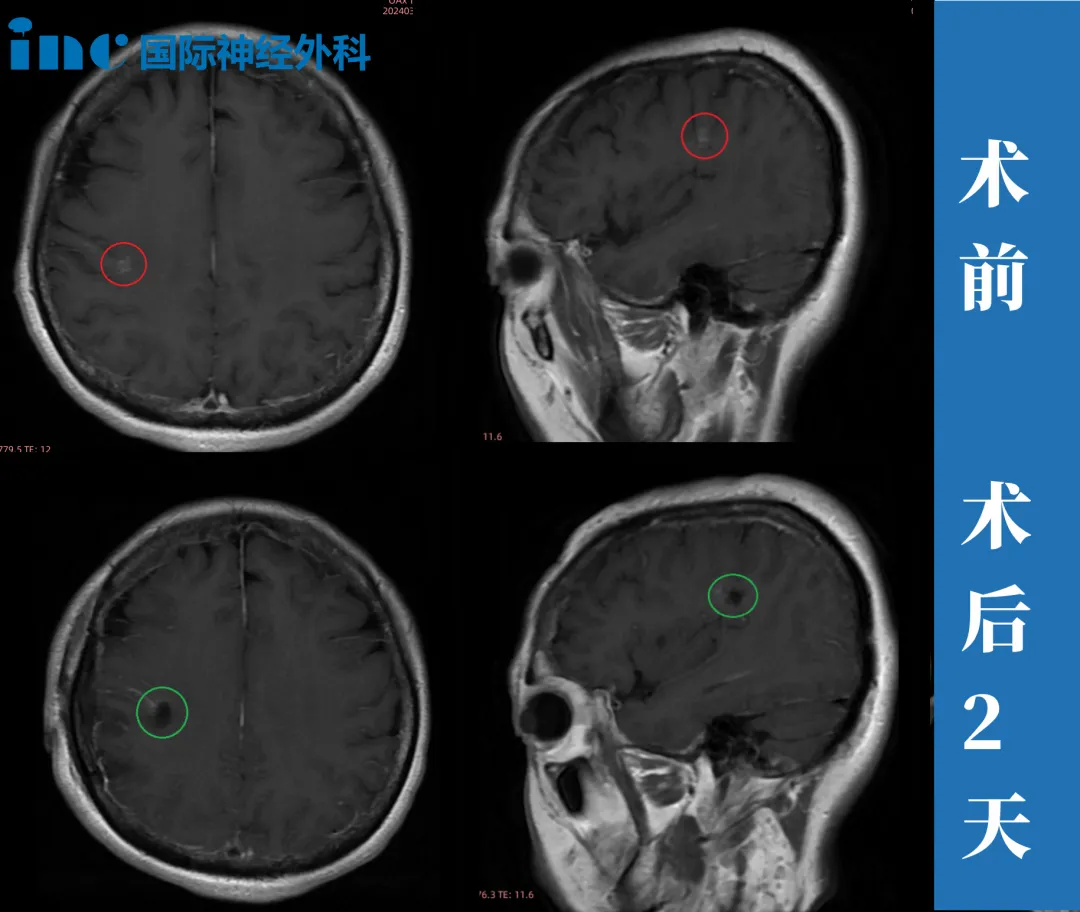

2024年3月28日,巴教授为欧女士量身定制的手术方案,目的就是在切除病灶的同时,最大程度保护功能区。

术后第1天,她就顺利转出ICU,回到普通病房;术后第2天,她已经能自主下床走路;术后第4天,手术切口恢复的良好,胃口也不错,喝了一碗鸡汤。